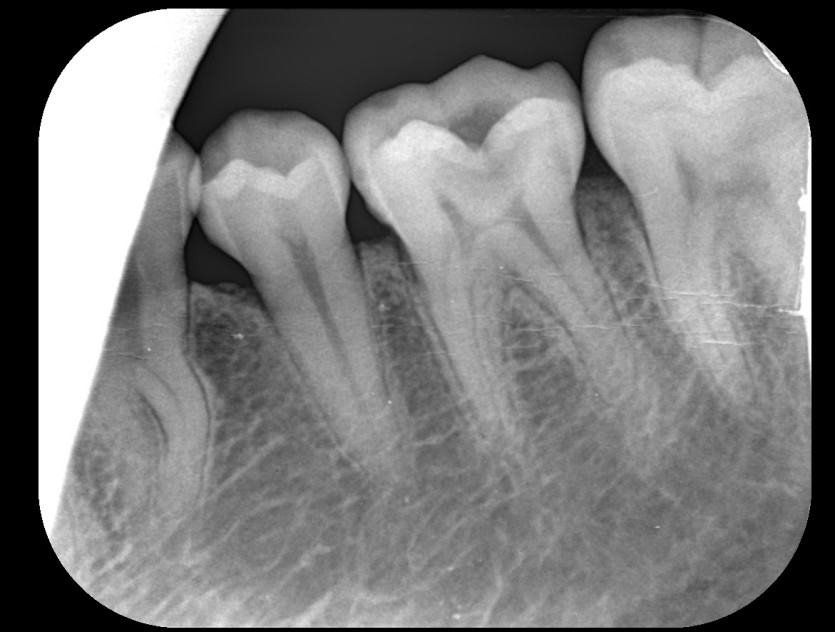

신경치료 사례